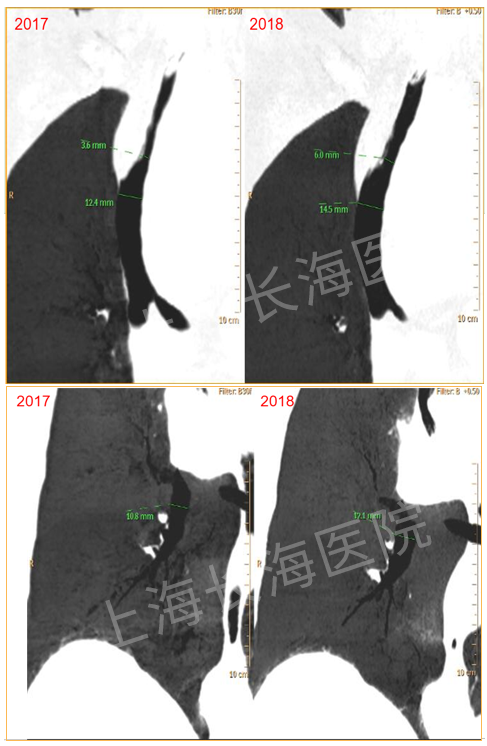

考虑患者高龄且心脏功能欠佳,气管镜操作风险极高,因此决定暂不处理,予振荡呼气正压治疗(OPEP装置)治疗,每日3次,同时予抗感染、雾化治疗。患者在2017—2018年没有采取任何的手术治疗措施,气道最窄处直径由3.6 mm增加到6 mm,除了主气道,左、右主支气管都有相应改善(图6)。随访患者生活质量较高。

图片

图6  患者气道直径变化